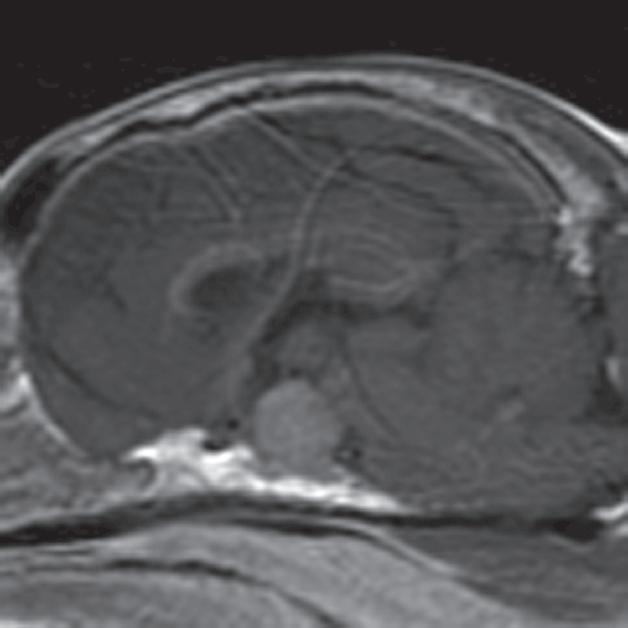

Badanie wykonano u 14-letniej, kastrowanej samicy szpica z przechyleniem głowy i występującym od niedawna chodzeniem w kółko w prawą stronę. Ryciny a–c to reprezentatywne obrazy w płaszczyźnie poprzecznej na poziomie dołu przysadki. Ryciny d–f to analogiczne obrazy w płaszczyźnie strzałkowej. Przysadka mózgowa była znacznie powiększona (wysokość = 10 mm, szerokość = 10 mm), izointensywna w obrazach T1-zależnych (a, d) i łagodnie hiperintensywna w obrazach T2-zależnych (b, e) w porównaniu z istotą szarą głęboką. Stwierdzono również poszerzenie układu komorowego (wentrikulomegalię), które może wynikać z częściowej niedrożności. Przysadka uległa jednorodnemu wzmocnieniu kontrastowemu (c, f), a w badaniu pośmiertnym wykazano, że miała postać dobrze odgraniczonej, kulistej masy (g). Potwierdzono, że zmiana była makrogruczolakiem przysadki